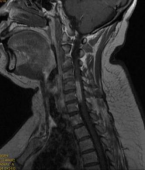

2.颈椎后路减压固定技术

颈椎后路减压技术适用于:脊髓型颈椎病伴发育性或多节段退变性椎管狭窄者;多节段OPLL;颈椎黄韧带肥厚或骨化所致脊髓腹背受压者。有节段性不稳定者可以同时行侧块钛板螺钉或经椎弓根螺钉内固定、植骨融合术。我科在区域内率先开展颈椎单开门、双开门技术,颈椎椎板切除减压椎弓根内固定术,均获得满意疗效。